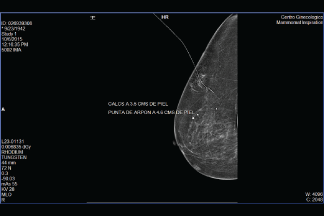

Marcaje de arpón

El estudio consiste en la inserción de una aguja especial en el área específica de la mama donde se localiza la lesión o masa, obteniendo una pequeña muestra del tejido, la cual es enviada a un laboratorio especializado donde se analiza la muestra y se determina la presencia o no de cáncer.

La aguja es insertada por un doctor especializado y certificado guiándose en tiempo real por las imágenes proporcionadas por mastógrafo o por ultrasonido para tomar la muestra exactamente de la lesión o masa. Este procedimiento es de mínima invasión, el cual no requiere hospitalización.